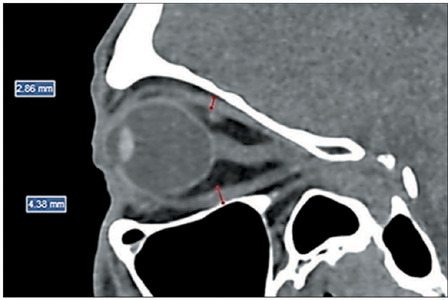

Objective: To assess the prevalence of changes on computed tomography (CT) in Graves' orbitopathy (GO) and to correlate those changes with disease activity, as well as with clinical and biochemical variables.

Materials and methods: This was a retrospective study, conducted at a tertiary hospital, of clinical, biochemical, and imaging data from consecutive patients with GO who underwent at least one orbital CT scan between July 2012 and December 2020. A single observer quantified the thickness of the extraocular muscles and the degree of proptosis. Clinical and biochemical variables were analyzed to determine whether they correlated with CT changes, GO activity, and GO severity.

Results: Our sample included data from 67 patients with GO (134 orbits), 50 (74.6%) of whom were female. There were positive correlations between the clinical activity score and increase in thyroid-stimulating factor/free thyroxine, between the severity of GO and the increase in the thickness of the extraocular muscles, and between the degree of proptosis and muscle thickness.

Conclusion: Orbital CT proved effective in detecting thickening of the extraocular muscles and proptosis in patients with GO, changes that correlated significantly with clinical and biochemical variables. Muscle thickening was associated with the severity of GO and could be a biomarker of the risk of vision loss.